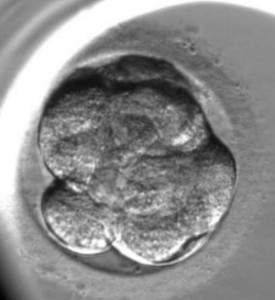

L’enregistrement du développement de l’embryon est le suivant :

La fin de la troisième division (l’apparition de huit blastomères)

Le commencement du compactage de l’embryon